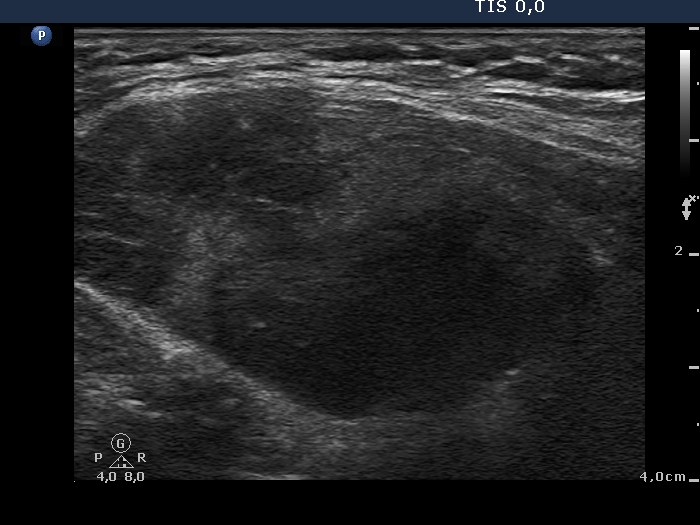

Ultrasonography. There was a large and several smaller, irregular, hypoechogenic lesions in the right lobe. The vascularization was decreased.